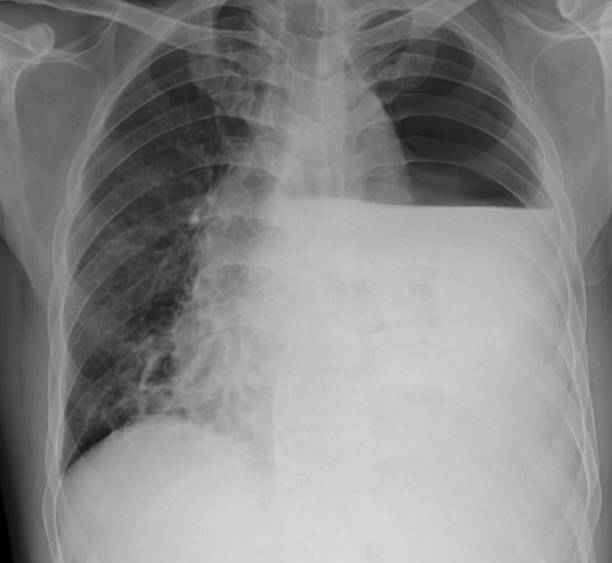

흉부 X선 검사

기흉이 의심되는 환자에게는 흉부 X선 검사를 실시하여 기흉이 있는지 확인할 수 있습니다. 이 방법은 비교적 쉽고 빠르게 기흉을 진단할 수 있습니다.

CT 스캔 검사

CT 스캔 검사는 폐의 3D 영상을 생성하여 누출된 공기가 있는 위치와 기흉의 원인을 파악할 수 있습니다.